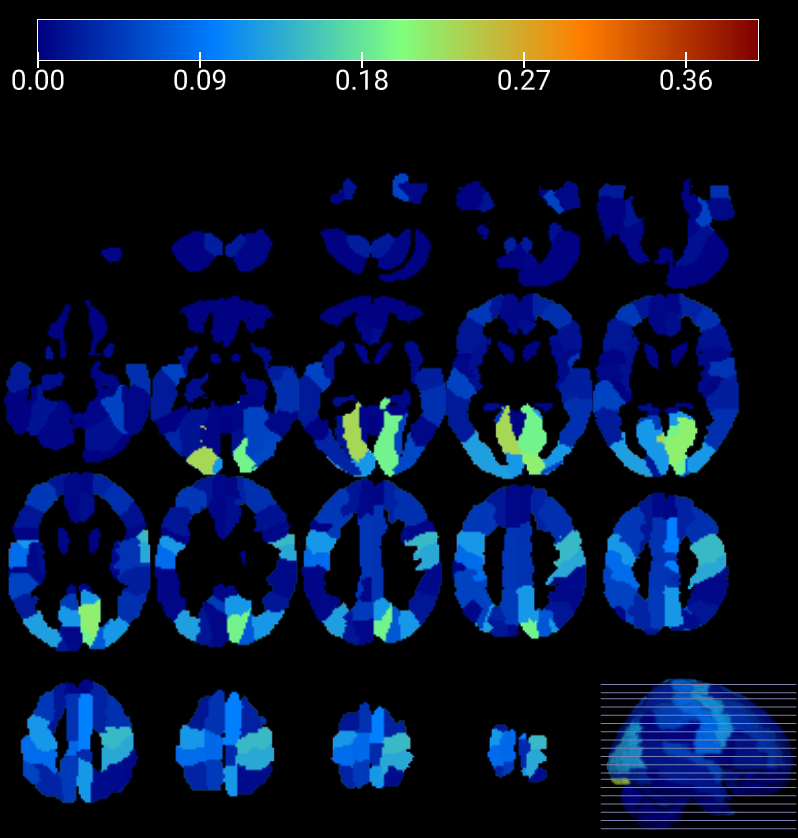

Refer to caption

(a)

(b)

Figure 10: SAM and SPM results for HC vs ASC all centers comparison. In the upper image, it is represented in orange the PDsubscript𝑃𝐷P_{D} at each brain region detected by SAM statistical method and in blue the PDsubscript𝑃𝐷P_{D} detected by SPM. In the lower image, the SAM and SPM comparison is presented, including their respective analyses with male subjects only.

At the bottom of Figure 10, we computed the PDsubscript𝑃𝐷P_{D} of the SPM voxelwise statistical framework and compared it to the one obtained with the SAM method. As clearly shown in the figure, SPM did not provide the nominal value of 0.05, indicating an overly super-conservative method. This behaviour is indeed persistent in the studies with larger samples sizes as shown in the next section. Following these results, the plimit-from𝑝p-value analyses did not reveal any evidence to reject the null hypothesis at the significance level.

Figure 10 provides a comparison of SAM and SPM results, visualizing regions identified as different by SAM along with their corresponding frequency values using an orange color map, and highlighting the number of voxels that manifested differences after the SPM contrast using a blue color map. SAM hightlights regions as Postcentral_R, Postcentral_L, Occipital_Mid_L, Occipital_Mid_R, Precentral_L, among others. Meanwhile, SPM highlights regions as Putamen_L, Putamen_R, Thalamus_R, Vermis_4_5, among others. Notably, the highest concentration of voxels detected by SPM was observed in regions where SAM indicated no or minimal differences, while regions exhibiting more significant differences according to SAM showed scarce significant voxels. Consequently, both methods did not individually establish statistically significant differences but contradicted each other in identifying regions with great disparities.

Figure 14 visually presents the comparison between SAM and SPM results, illustrating the regions identified by SAM as having significant differences along with their corresponding frequency denoted by an orange color map, as well as the most significant voxels detected by SPM, denoted by a blue color map.

Figure 14: Comparison of SAM and SPM results for HC vs ASC comparison at NYU center. In orange, the differences in brain regions detected by SAM statistical method. In blue, the differences detected by SPM.

Currently, numerous studies have investigated the application of deep learning techniques using the ABIDE I database to classify autism, wherein they have identified specific brain regions that exhibit notable correlations. These regions often manifest in the posterior section of the brain, including the Occipital Pole, Precuneus Cortex, Intracalcarine Cortex, Left Lingual Gyrus, and others [9, 24, 61, 42, 28, 17]. These areas hold potential significance in our image comparison study. Focusing solely on the HC vs ASC comparison, the SAM analysis has revealed that the regions displaying a greater frequency of significant differences, both in the study based on the patients’ condition and in the study conducted at the NYU center (yielding the most favorable outcomes), are predominantly located in the posterior regions of the brain. Noteworthy areas include Occipital_Mid_L, Calcarine_R, Cuneus_R, Lingual_L, Lingual_R, among others. Additionally, the Postcentral region stands out in the SAM analysis and in certain publications. Thus, these areas may align with those exhibiting robust correlations in previous studies. However, the SPM analysis reveals that the majority of differences, or areas with the highest voxel concentration after contrast, are situated in the central and inner regions of the brain. This pattern is observed both in the analysis based on the patients’ condition and in the study encompassing centers that encountered no issues during the analysis. Noteworthy regions encompass Putamen_L, Putamen_R, Thalamus_L, Thalamus_R, Frontal_Sup_R, Temporal_Mid_R, among others. Figures 10 and 14 prominently depict the regions of interest identified by both mapping methods, providing a clear visual representation.